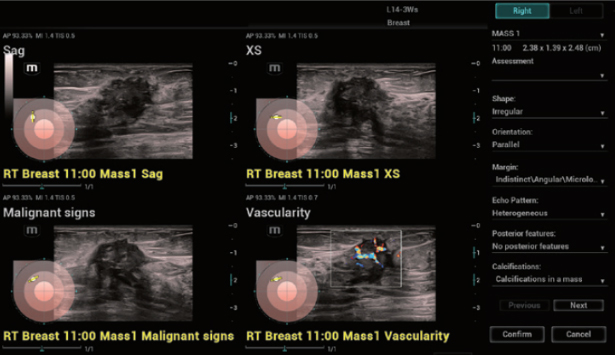

HiFR STE новообразования молочной железы

HiFR STE новообразования молочной железы